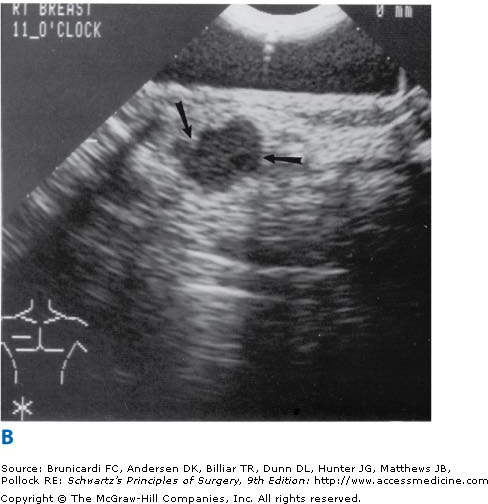

Meme kanserinde 20 yaşından sonra 41 yaşına kadar her kadın periodik olarak her yıl kontrol edilmelidir ve meme us ile kontrol edilip memede kitle olup olmadığı bu kitlenin kistik veya solit olup olmadığı solit kitleninde maliğn özellik taşıyıp taşımadığı saptanmalı, maliğn özellik taşıyorsa biopsi yapılmalıdır. 41yaşından büyük hastalarda ise meme us’na a mamografi ilave edilmelidir. Mamografi yapılamayan hastalarda meme MR tanıda yardımcı olmakta maliğn şüpheli vakalarda biopsi uygulanmaktadır.

* Meme biopsisi ile kesin tanı konur. (Açık biopsi – true – cut iğne biopsisi- bilgisayar işaretleme ile yapılan biopsi).